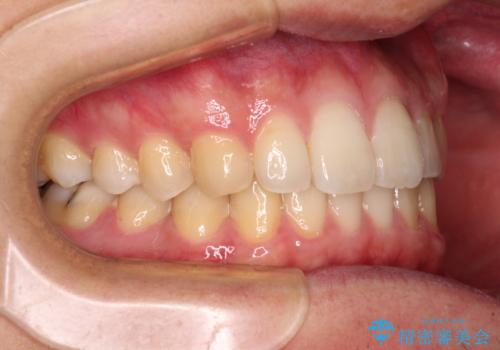

前歯のクロスバイトと抜歯が必要な奥歯の虫歯 インビザラインとインプラント治療

- 前歯のクロスバイトと、大学生のころから放置している虫歯を気にして来院された患者様です。

マウスピースでの矯正治療を希望されていましたが、前歯のクロスバイトは不十分な仕上がりや歯髄壊死などのリスクが高くなるため、術前にワイヤーで大まかに整えてからインビザラインにて矯正治療を行うこととしました。

奥歯の虫歯は抜歯が必要であったので、矯正治療前に抜歯をし、矯正治療と並行してインプラントによる補綴治療を行うこととしました。